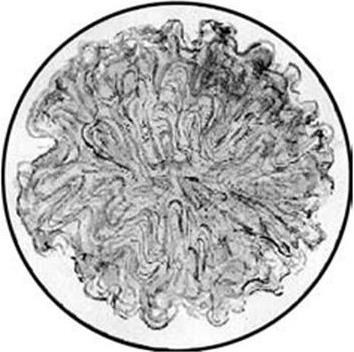

Колония сибирской язвы